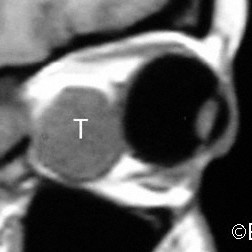

Choroidal Melanoma

MRI SAGITTAL SECTION demonstrates massive extrascleral tumor extension (T).